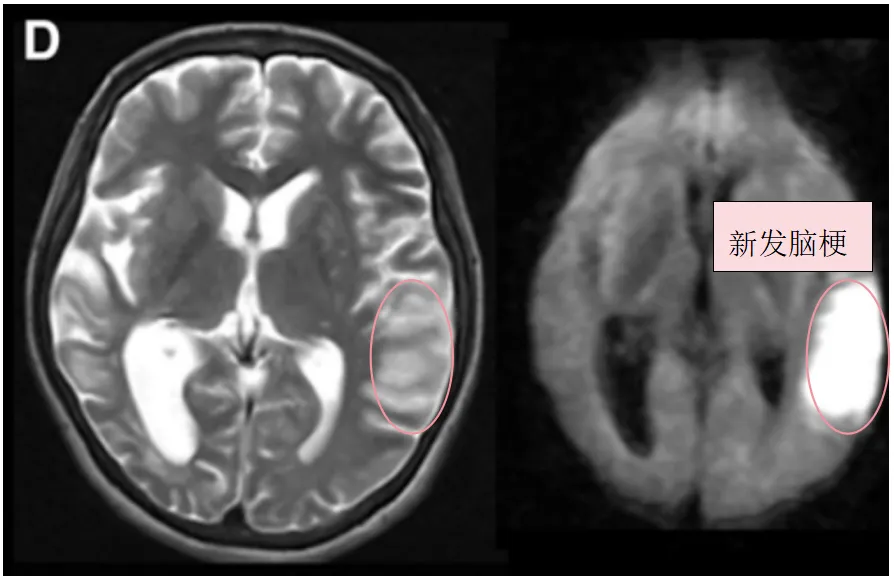

1个月后,幸子因构音障碍和右腿无力入院,并在左额叶出现新的脑梗死(图1C,D)。随后出现甲状腺风暴。(fT4 3.91 ng/ml,fT3 10.09 pg/ml)

图1D:入院3天后术前T2、DWI序列显示左侧颞叶进一步新发脑梗死